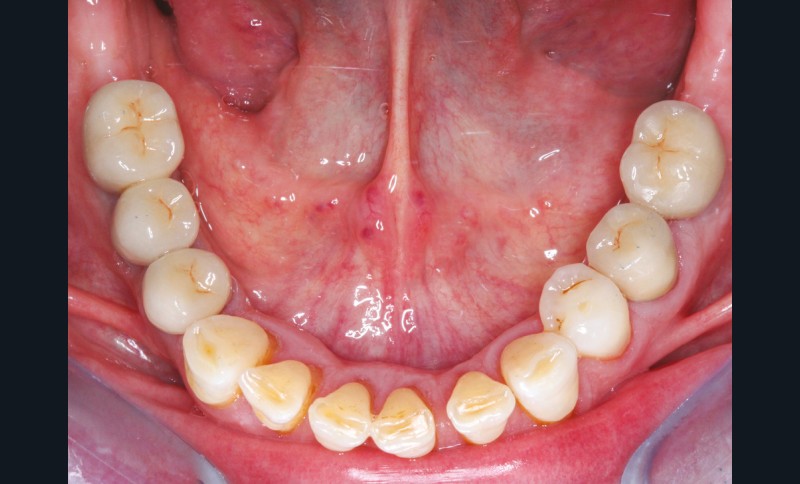

Le principe de protection mutuelle implique que les dents postérieures protègent les antérieures lors de la mastication. Des extractions non compensées de molaires, par exemple, entraîneront une hypersollicitation des antérieures et une usure importante du fait du principe de calage ainsi qu’un risque de perte de dimension verticale (fig. 10 à 13).

Des extractions multiples non compensées peuvent aussi occasionner une usure excessive des dents restantes, en raison de leur sollicitation occlusale trop importante.